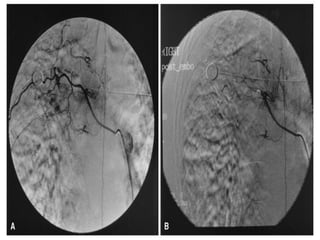

Bronchial artery embolization